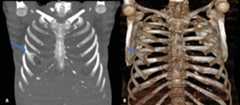

Foramen rib prevalence was found as 0.09%. The only case (0.45%) with a foramen rib variation was a 26-year-old female. The foramen was located symmetrically on the first ribs (Fig. 5).

Figure 5.Presence of a single foramen on the first rib on both sides on the coronal computed tomography image (A) and three-dimensional image (B).